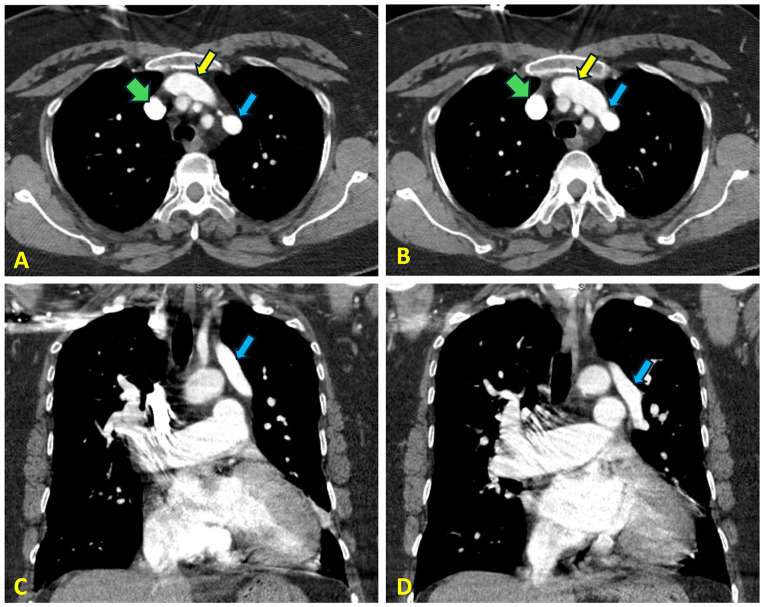

Partial anomalous pulmonary venous return (PAPVR) involving the left upper lobe pulmonary vein is an exceptionally rare congenital anomaly that, if untreated, can lead to pulmonary hypertension (PH). Its nonspecific clinical presentation often results in delayed diagnosis. We report the case of a 58-year-old woman who initially presented with progressive dyspnea and was diagnosed with group III pulmonary hypertension attributed to obstructive lung disease. Two years later, she returned with similar symptoms after discontinuing diuretic therapy. Further evaluation uncovered a previously undetected anomalous left pulmonary vein draining into the left innominate vein. This case highlights the diagnostic challenges of PAPVR, its role in contributing to PH, and the critical need for high clinical suspicion and comprehensive evaluation in patients with unexplained pulmonary hypertension.